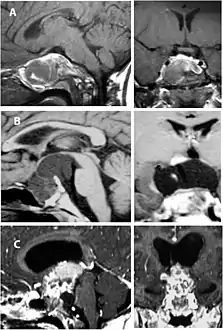

Imaging scans for craniopharyngioma

A physician can conduct a few scans and tests to diagnose a person with craniopharyngioma.[19] High-resolution magnetic resonance imaging (MRI) is commonly used as a diagnostic tool; however, computer tomography (CT) remains the gold standard imaging choice for craniopharyngioma diagnosis as it can detect the severity of the calcification within the tumour.[20]

In some cases, a powerful 3T (Tesla) MRI scanner can help define the location of critical brain structures affected by the tumor. The histologic pattern consists of nesting of squamous epithelium bordered by radially arranged cells. It is frequently accompanied by calcium deposition and may have a microscopic papillary architecture. A computed tomography (CT) scan is also a good diagnostic tool, as it detects calcification in the tumor.[21]

CT scan showing a craniopharyngioma

Enhanced T1 weighted MRIs of craniopharyngiomas